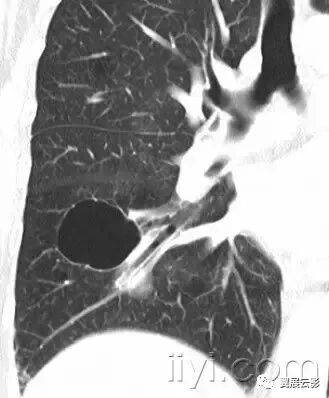

附图为小叶中心性肺气肿

十八、小叶中心性:

解剖:小叶中心性用于描述次级肺小叶的支气管血管束中心区域。病理学上也用这一术语描述终末小支气管远端,位于呼吸性细支气管和肺泡管中心的病变。

CT:正常次级肺小叶中心的点状或者线状的密度增高影,胸膜下25px范围内最明显,代表小叶内的动脉,直径约1mm。

小叶中心性异常包括(1)结节(2)树芽征,提示小气道病变(3)由于临近间质的增厚或者浸润导致小叶中心结果更加清晰(4)小叶中心性肺气肿导致的异常低密度。